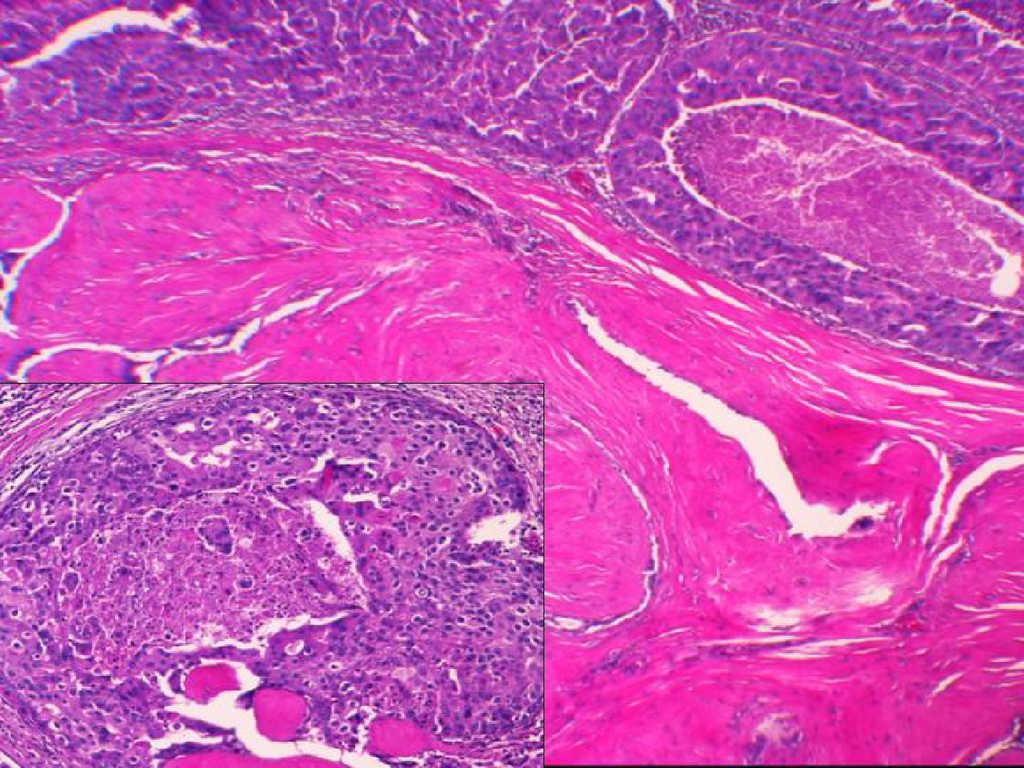

Caso 3Mujer de 60 años, sin antecedentes de interés, remitida a nuestra unidad por cambios mamográficos indicio de malignidad en una lesión nodular conocida previamente, no palpable, localizada a las seis de la mama derecha. El examen físico fue normal. La biopsia con aguja gruesa no obtuvo material suficiente y se propuso biopsia guiada por arpón. El estudio anatomopatológico reveló un fibroadenoma de 1,6cm que alojaba un carcinoma lobulillar invasor (figura 2). La paciente no aceptó el tratamiento quirúrgico conservador y fue sometida a mastectomía radical modificada. No se evidenciaron metástasis en ninguno de los 21 ganglios analizados.

Figura 2. Caso 3. Neoplasia lobulillar infiltrante con afección sólida de los ductos en el seno de una lesión fibroadenomatosa. Aspecto característico con filas de células tumorales infiltrantes en el interior de la estroma mamaria (H-E, ×10 y ×40).